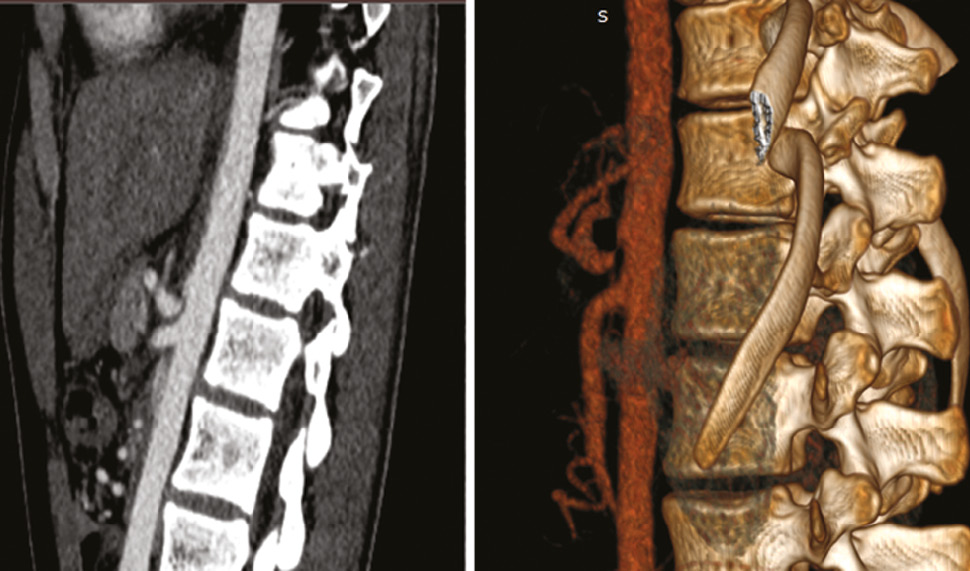

Учитывая данные анамнеза и увеличенную скорость кровотока по чревному стволу, для подтверждения стеноза следующим этапом выполняли МСКТ с внутривенным усилением (препарат «Визипак»). Наиболее показательной считалась картина в сагиттальных срезах. При анализе данных МСКТ изучалась анатомия чревного ствола и его ветвей, особенности их строения с определением зоны сужения и постстенотического расширения. Полученные данные подтверждались при 3D-реконструкции (рис. 1).

Рис. 1. Компьютерная томография с 3D-реконструкцией компрессионного стеноза чревного ствола

Fig. 1. A CT picture of compression stenosis of the celiac trunk